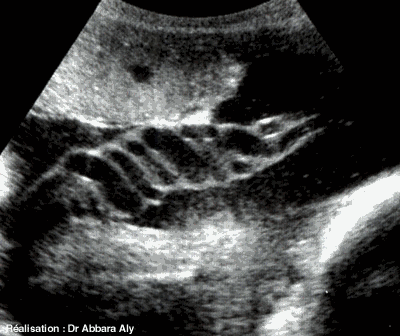

Coupe du cordon ombilical (trajet complex)